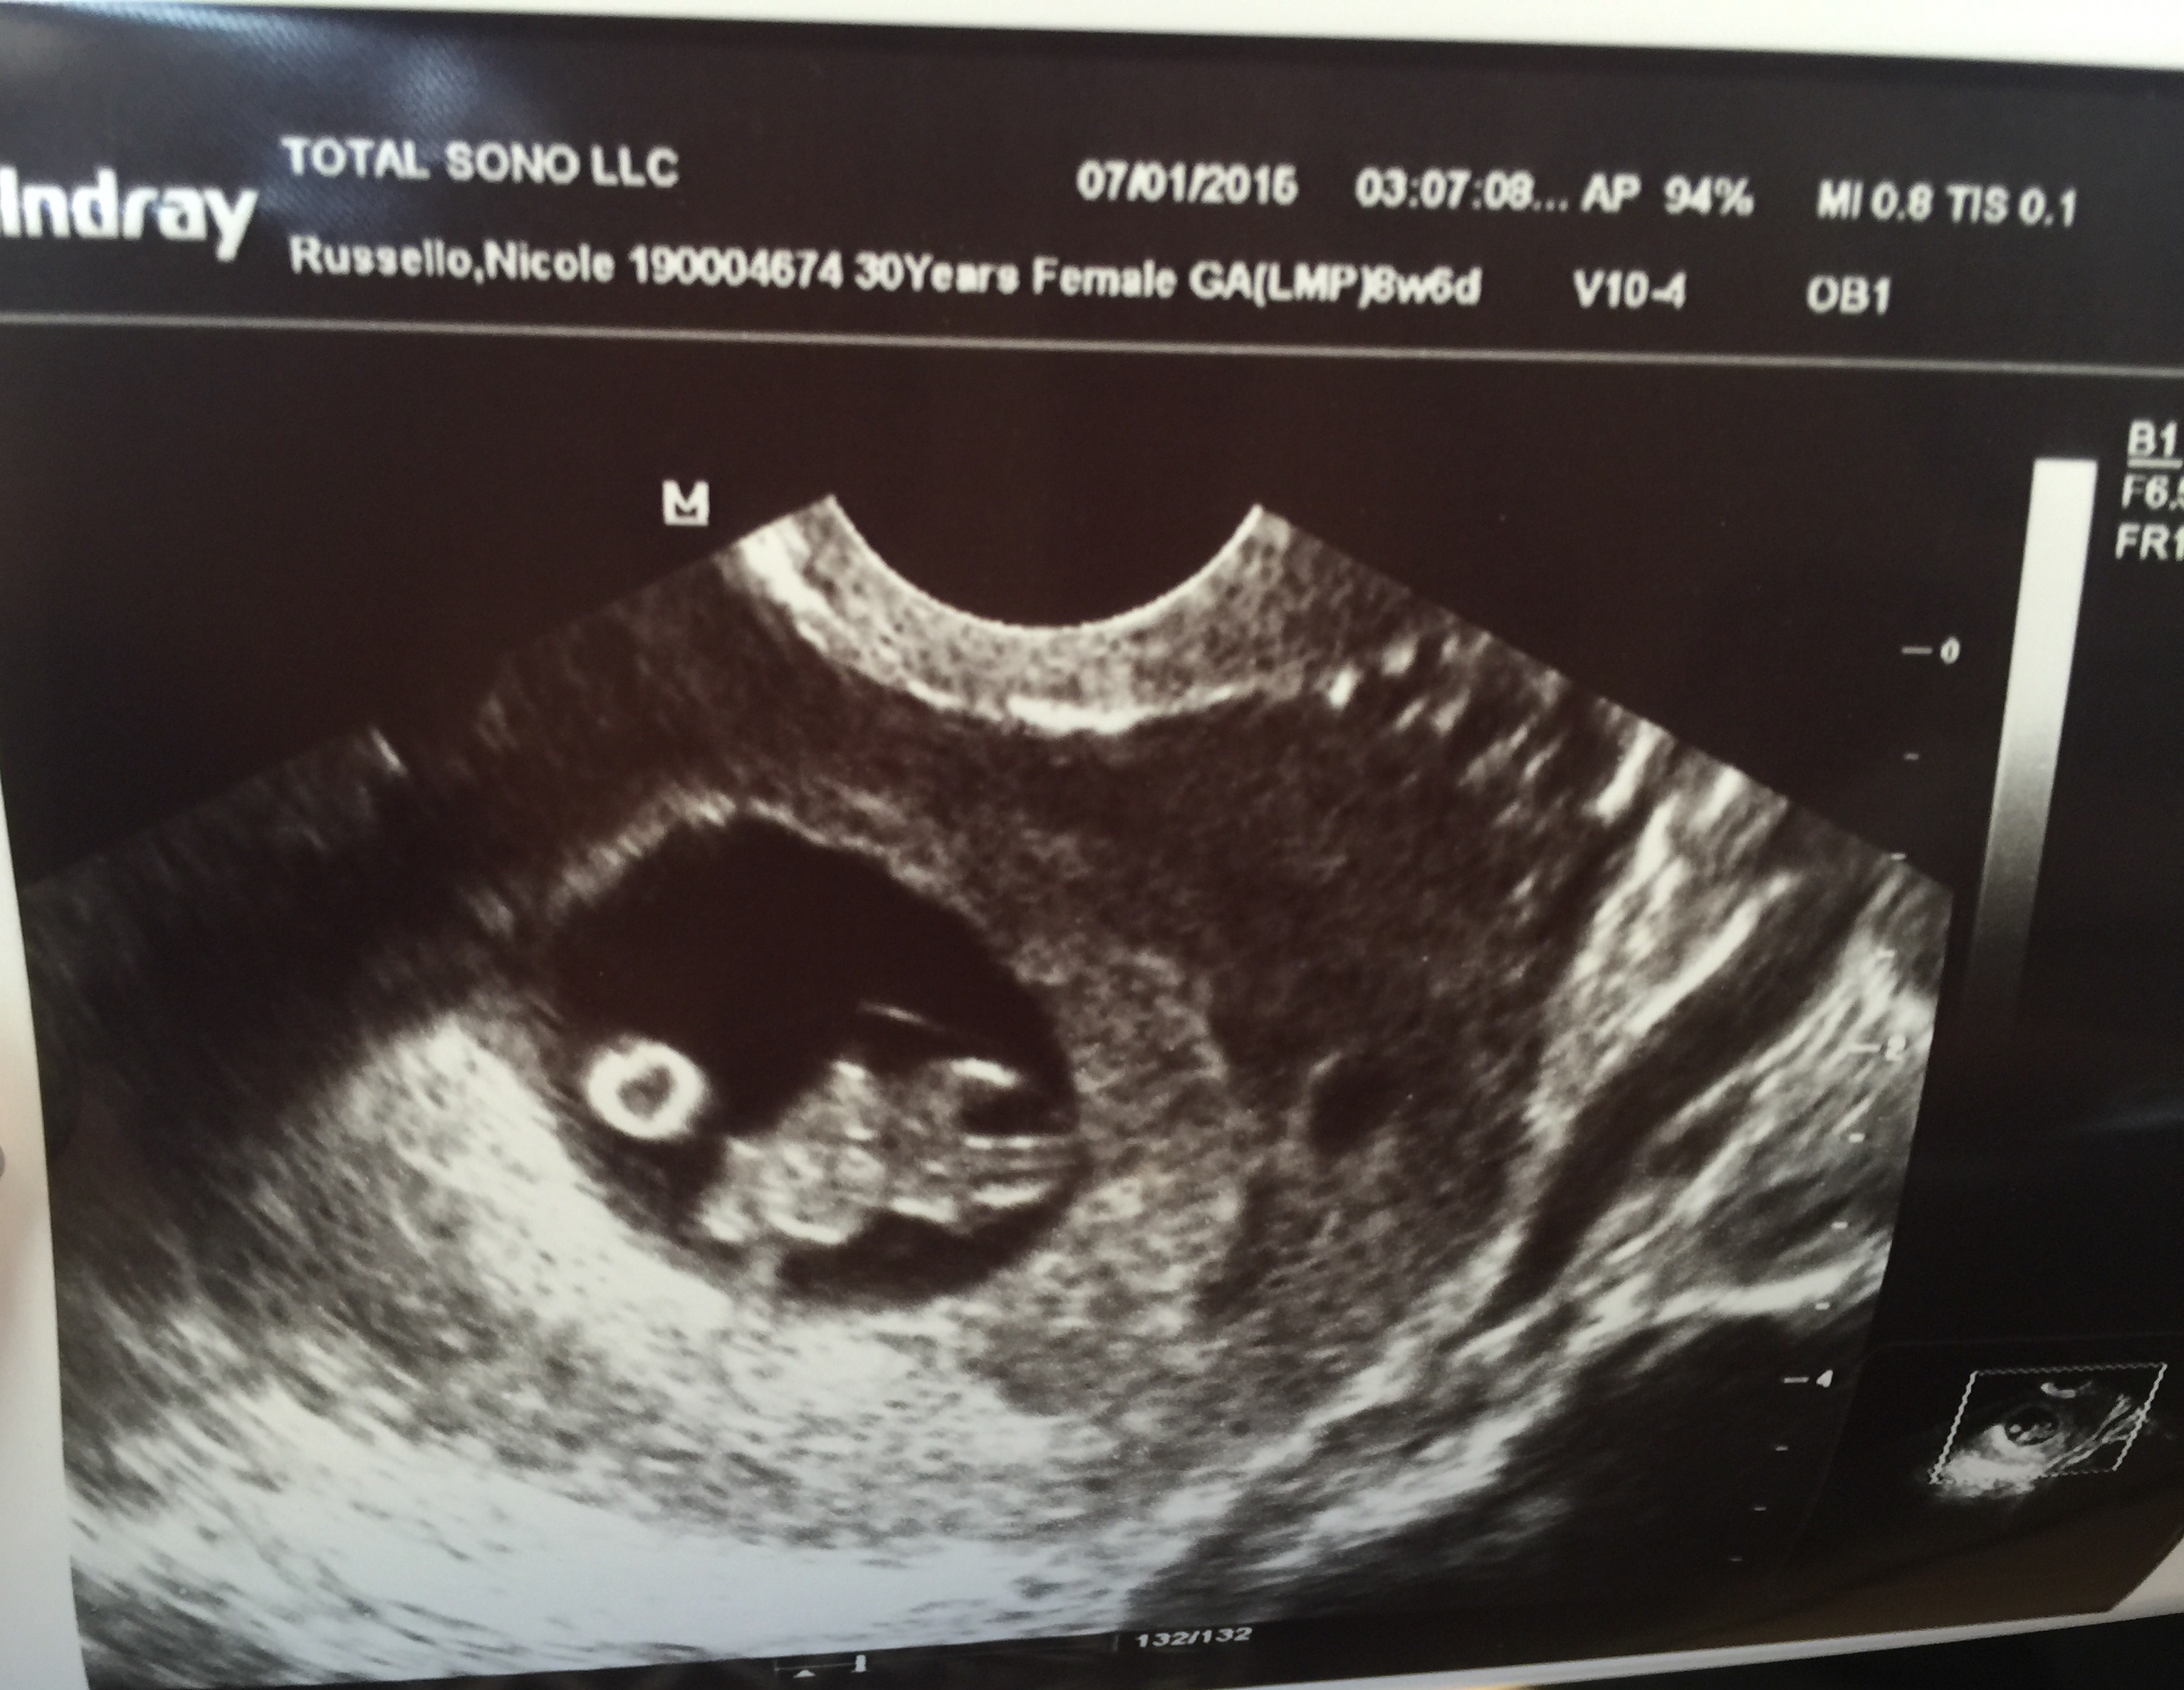

• Our sweet bean :) at 8 weeks 5 days

• @martin91 make sure you crop your photo because it's got some of your personal information on the top

This is my first post, but I am due 2/5/16 with my first little one. Heart rate was 167, and I'm 9w2d right now. US was taken at 8w4d